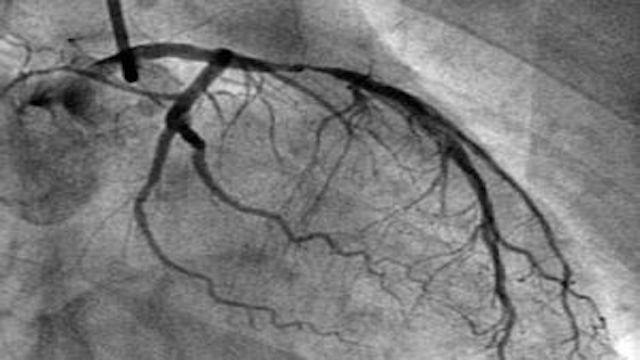

いよいよ心臓血管検査の王様についてお話ししましょう。冠動脈造影は私よりずっと古く,1959年にアメリカのクリーブランド・メディカル・センターのSones博士が最初の冠動脈造影を完成させてから,56年近い歴史がある。開始以来、冠動脈造影はその直感的で客観的な特徴から、冠動脈疾患のゴールドスタンダードとなっています。

冠動脈疾患の診断におけるゴールドインデックスの意義は、イエスかノーかという皇帝の遺言のようなものである。冠動脈についてどのような検査が行われたかにかかわらず、冠動脈造影が行われた以上、すべては冠動脈造影の結果に左右される。冠動脈造影検査とは、大腿動脈または橈骨動脈からボールペンの芯のような太いカテーテルを挿入し、冠動脈の開口部に入れ、造影剤を注入して画像を現像する方法で、造影剤下で冠動脈血管の配列、数、変形を観察し、冠動脈病変の有無、重症度、範囲を評価し、冠動脈の攣縮、側枝循環の有無など冠動脈の機能的変化を評価し、同時に冠動脈の左側も考慮して、冠動脈の機能的変化を評価することです。冠動脈の攣縮や側枝循環を含む冠動脈の機能的変化を評価し、同時に左心機能の評価も考慮することができる。この検査は基本的に電気生理学的検査を除くすべての心臓関連検査を網羅していると言える。

2、冠状動脈造影検査:これは侵襲的な検査で、動脈穿刺を通して、カテーテルを冠状動脈の開口部に入れ、造影剤を注入し、X線の下で血管内の充満状況と血流速度を観察します。このような検査は直接血管内の状況を見ることができるので、冠状動脈性心臓病の診断の黄金指標ですが、欠点はこのような検査は侵襲的な検査であるということです;

6.冠動脈造影(経皮経動脈的冠動脈造影法)手順動脈穿刺(手首の橈骨動脈または太ももの付け根の大腿動脈)で冠動脈の開口部にカテーテルを送り、ヨード造影剤を注入して冠動脈の形態と血流を観察し、一般に50%以上の狭窄があれば冠動脈疾患と診断する。この方法は現在、冠動脈疾患を診断するための "ゴールド・スタンダード "である。その利点は、正確であること(もちろん、投影の角度や医師の経験、血管の変形などにより、不正確な場合もある)、問題が発見された直後にバルーン拡張術やステント留置術(その他の手技も含む)により冠動脈を開いて血液供給を改善し、問題の発見と治療を同時に行えることである。この方法は低侵襲で、確かな技術と優れた安全性を備えた手技である。しかし、手技である以上、傷害やリスク、造影剤と同じ問題がある。

- 冠動脈造影は高度な配管工事である。冠動脈造影の原理は冠動脈CTAと似ているが、冠動脈造影は侵襲的な検査で、手や大腿の動脈から心臓の冠動脈まで管を送り、冠動脈に直接造影剤を注入し、冠動脈の形態をフィルムカメラで見る(DSA)。この検査は冠動脈疾患の診断のゴールドスタンダードであり、冠動脈の主幹や太い枝だけでなく、細い枝の一部も見ることができる。冠動脈疾患の診断手段としてだけでなく、冠動脈インターベンション治療と呼ばれる、このカテーテルを通してバルーンやステントなどを送り込んで治療する手段としても使用できるため、何よりも高度な配管工と言われている。